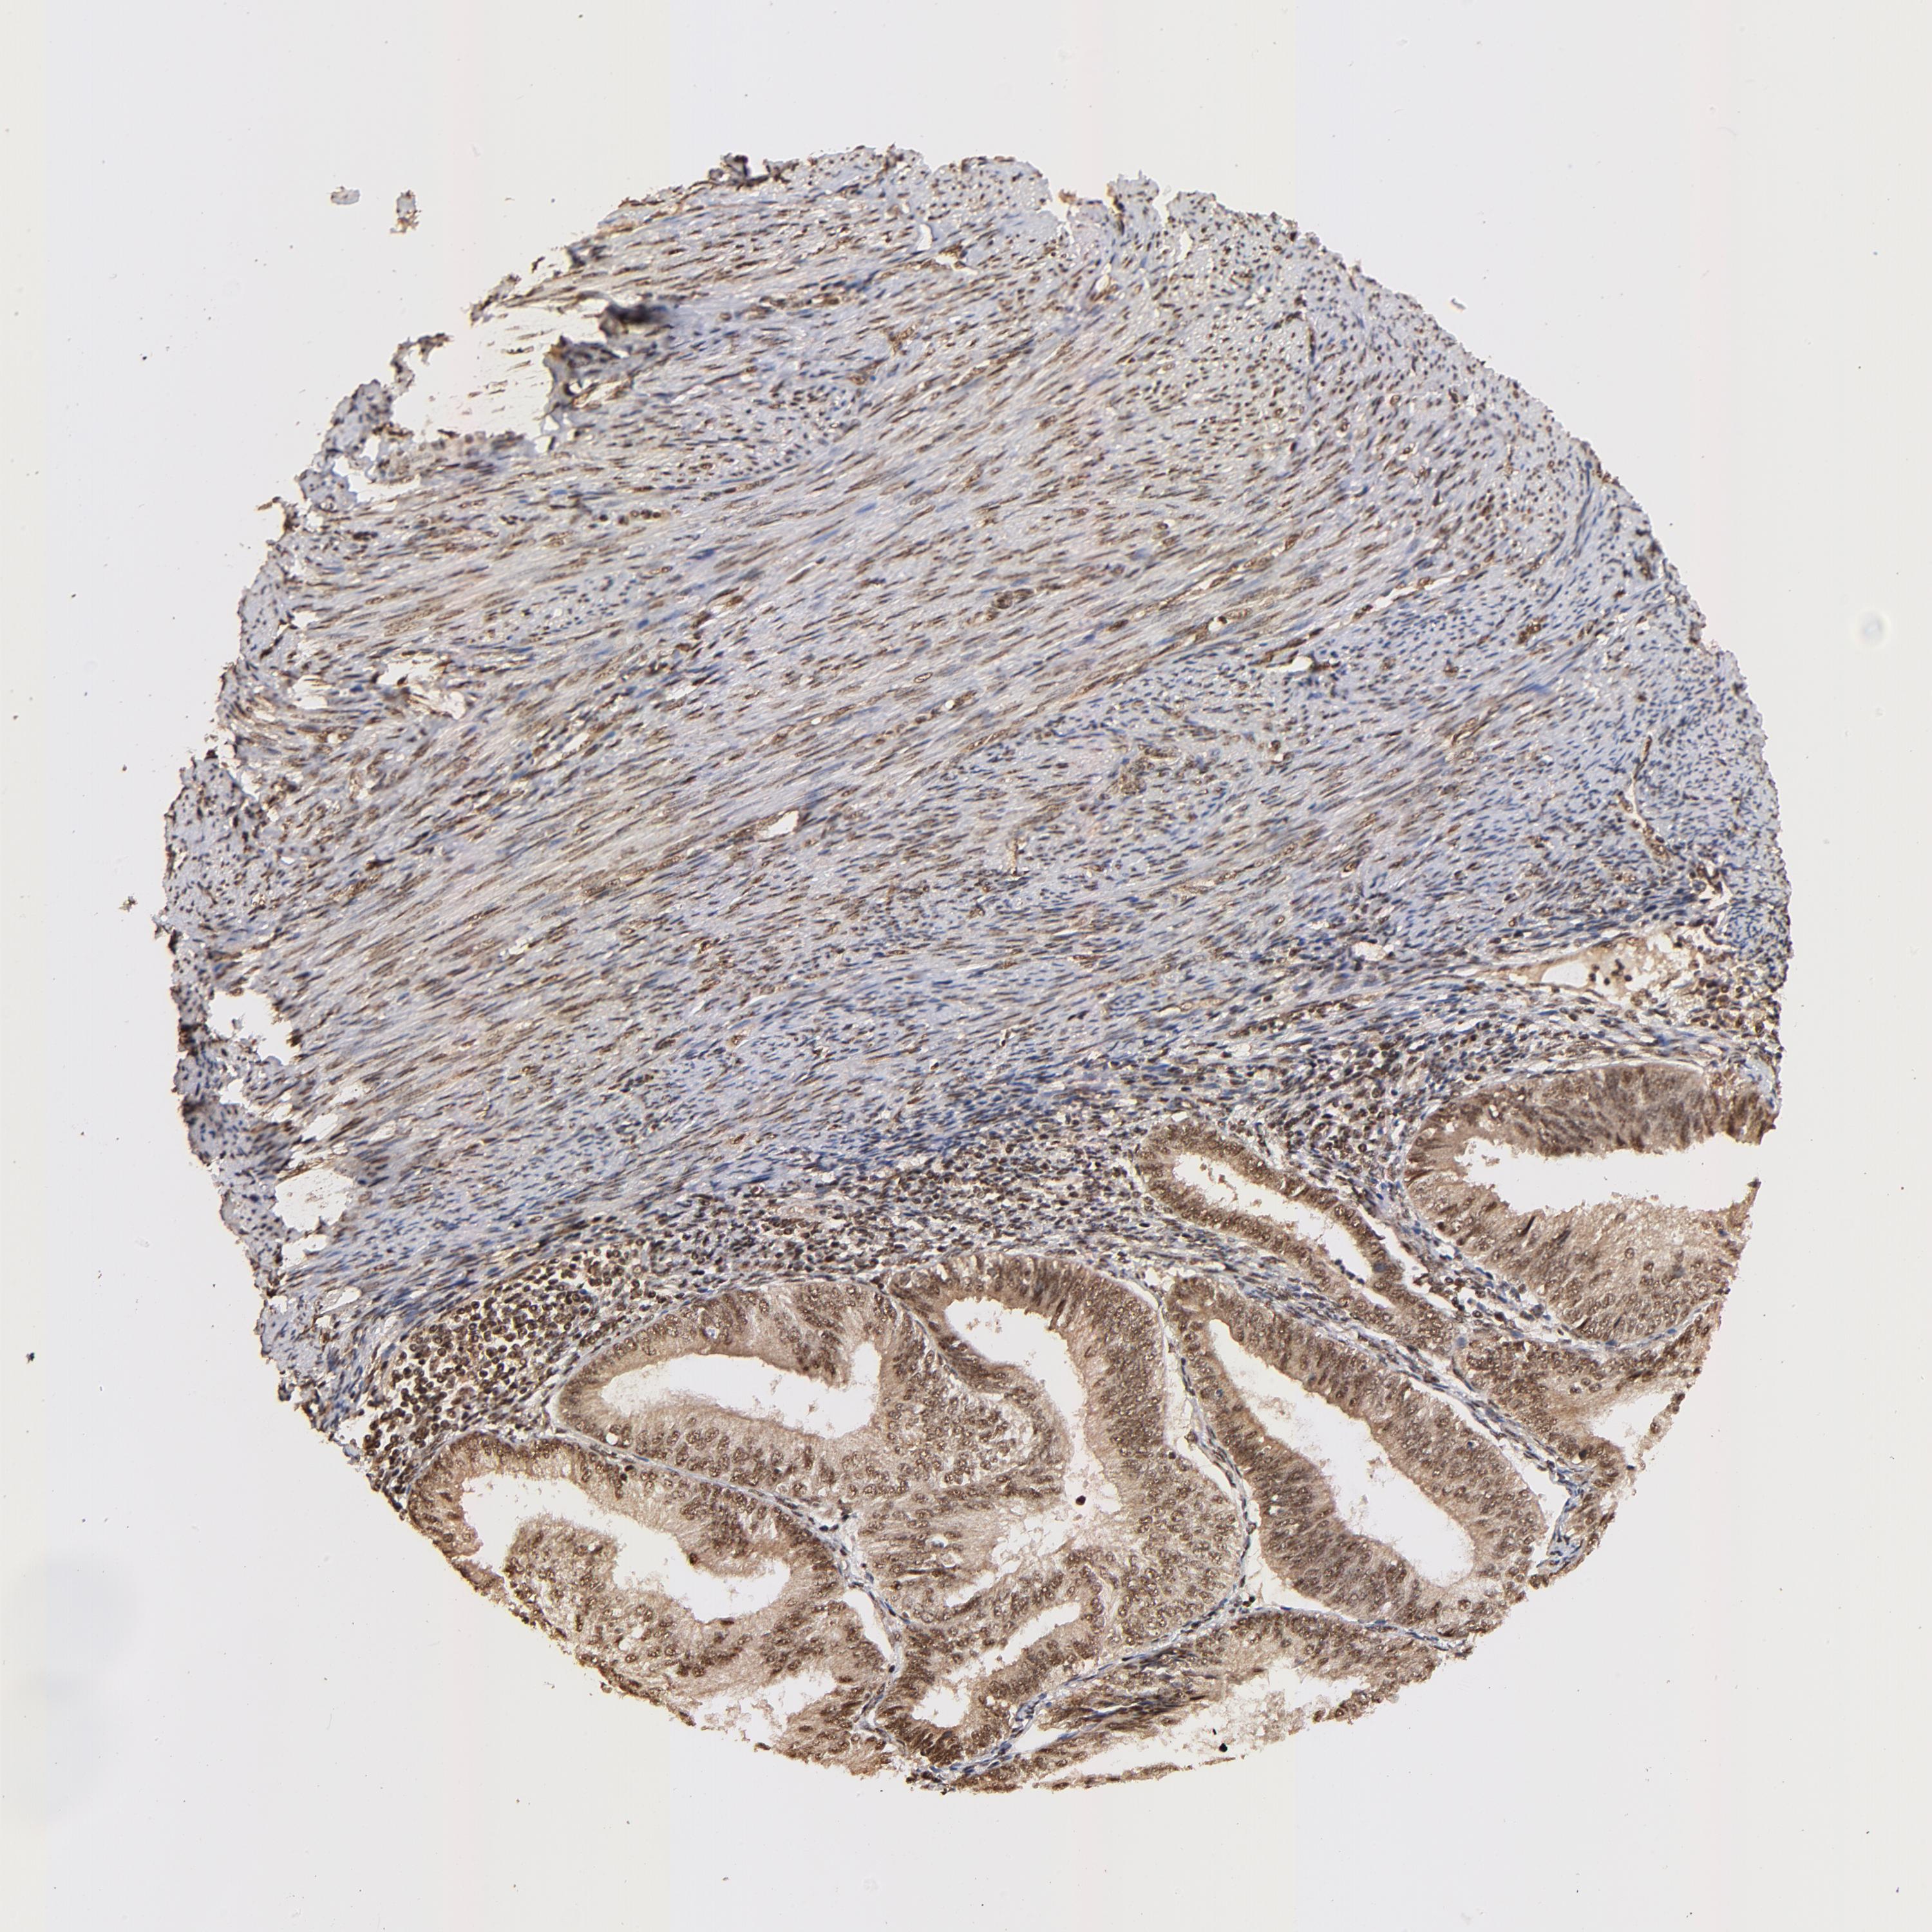

ENDOMETRIAL CANCER - Protein expressioni

A mouse-over function shows sample information and annotation data. Click on an image to view it in a full screen mode. Samples can be filtered based on level of antibody staining by selecting one or several of the following categories: high, medium, low and not detected. The assay and annotation is described here.

Note that samples used for immunohistochemistry by the Human Protein Atlas do not correspond to samples in the TCGA dataset.

Antibody stainingi

Antibody staining in the annotated cell types in the current human tissue is reported as not detected, low, medium, or high, based on conventional immunohistochemistry profiling in selected tissues. This score is based on the combination of the staining intensity and fraction of stained cells.

Each image is clickable and will lead to virtual microscopy that enables deeper exploration of all samples and also displays staining intensity scores, fraction scores and subcellular localization as well as patient and tissue information for each sample.

Antibody HPA003184

Antibody HPA003185

Staining

High

Medium

Low

Not detected

Intensity

Strong

Moderate

Weak

Negative

Quantity

>75%

75%-25%

<25%

None

Location

Nuclear

Cytoplasmic/membranous

Cytoplasmic/membranous,nuclear

Adenocarcinoma, NOS